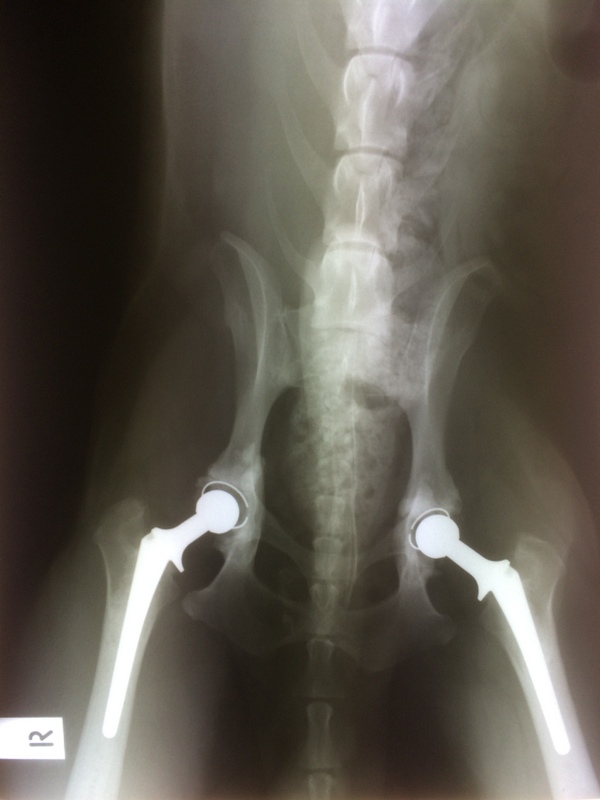

bianca.a Posted July 8, 2014 Author Share Posted July 8, 2014 Oh thank you both so much ((hugs)) Yes it has been way to cold for this chicken :laugh: Specialist reviewed his 6 week xrays (done by a local vet) and yesterday I got the all clear to start walking him 2 half an hour walks per day for one month, then 2 one hour walks per day!!!!!! Link to comment Share on other sites More sharing options...

bianca.a Posted July 8, 2014 Author Share Posted July 8, 2014 These were done by a locum vet locally and aren't digital. Link to comment Share on other sites More sharing options...

persephone Posted July 8, 2014 Share Posted July 8, 2014 YAY :) what beautiful Xrays to see Link to comment Share on other sites More sharing options...

BC Crazy Posted July 8, 2014 Share Posted July 8, 2014 Yaaaaa !!!!!! What wonderful news Biannca. Coopers got the all clear...He can finally go for short walks & slowly regain his strength. You have done a fantastic job taking care of him. It must of been very difficult for you to witness your boy suffering. Coop has the best looking hips in town now LOL Go enjoy your lovely boy :) Link to comment Share on other sites More sharing options...